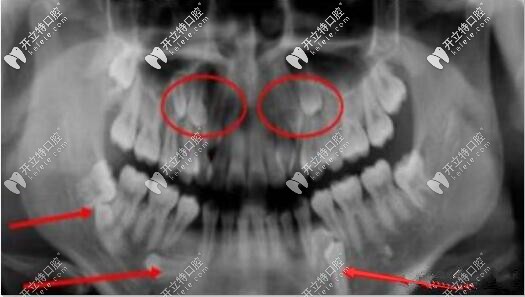

智齒口腔全景片

此類智齒需要拔除

如圖所示這樣沒有正常萌出,傾斜、阻生的智齒,容易造成食物鑲嵌堵塞,容易齲壞需要盡早拔除。